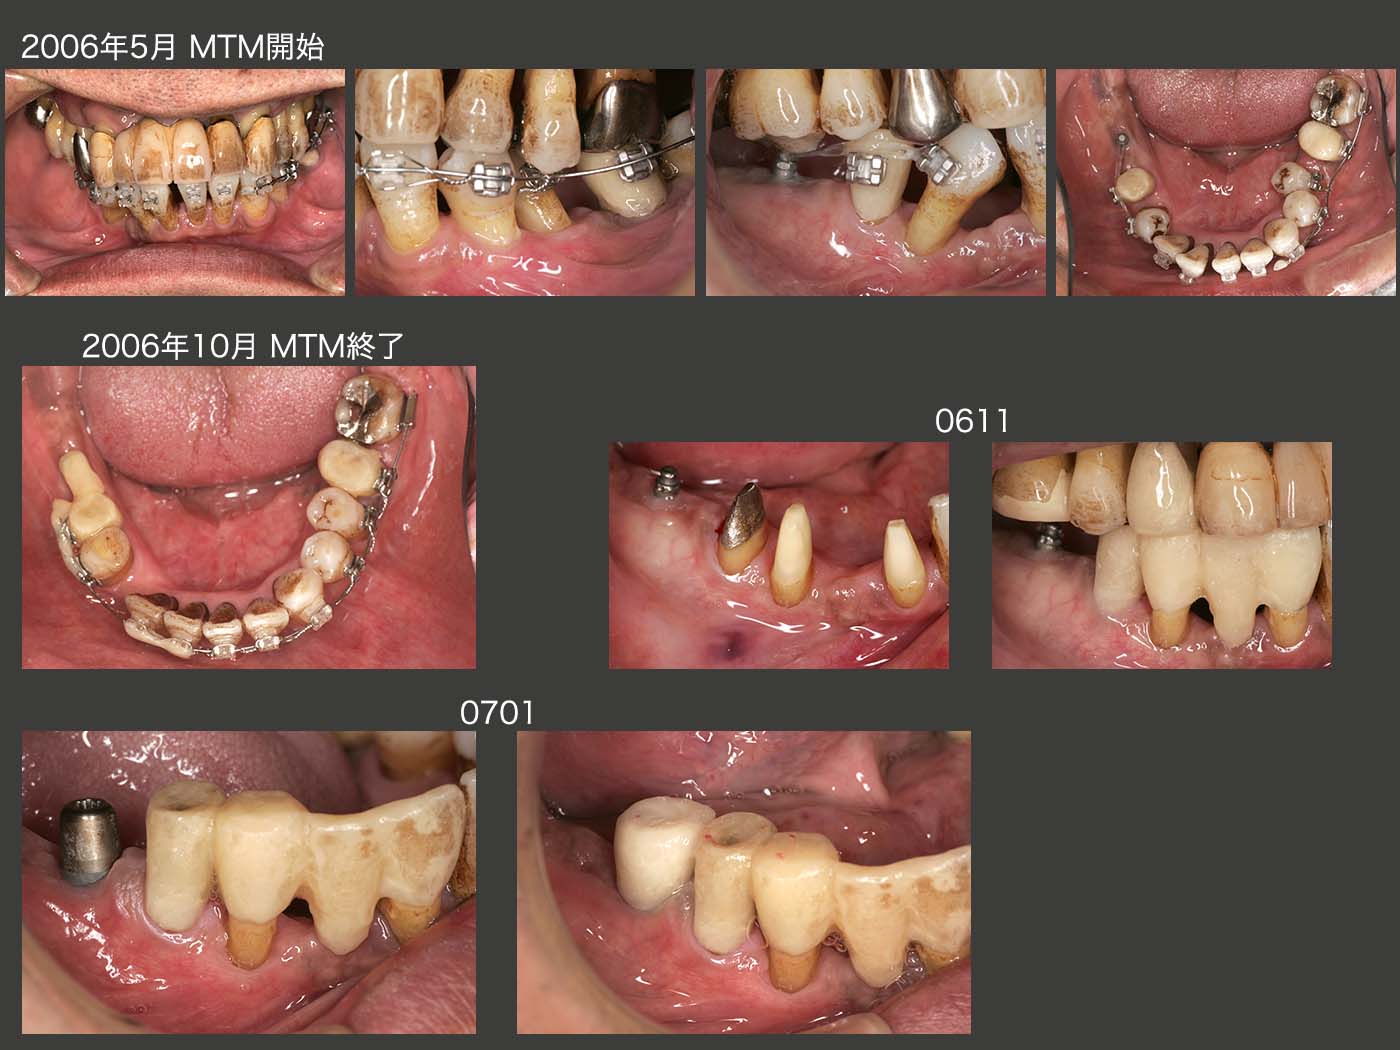

まず,近心傾斜している右下4および歯列から外れている左下5のアップライトを目指し,2006年5月,歯科矯正を開始し,10月終了した.これで,右下4の抜髄は避けることができた.しかし,右下⑤④3②のブリッジのみで,右側の咬合を全て担うのは難しいと考え,12月に右下6部にインプラントを1本植立した.但し,ブリッジとインプラントとを連結固定する必要まではないと考えた.

2007年6月,右側の咬合支持を確保したところで初診終了となった.アップライトした左下5を隣在歯と固定するか迷ったが,今回は固定せず経過をみることにした.喫煙の習慣があり,歯周ポケットも存在することから決して予断が許されない症例であると認識していた.

07年10月,1回目のリコール時に右下のインプラントのポケットが10mmの値を示し,唖然とした.しかし,ここでいきなり再治療とはいかず,患者さんによく説明し,経過をみることになった.